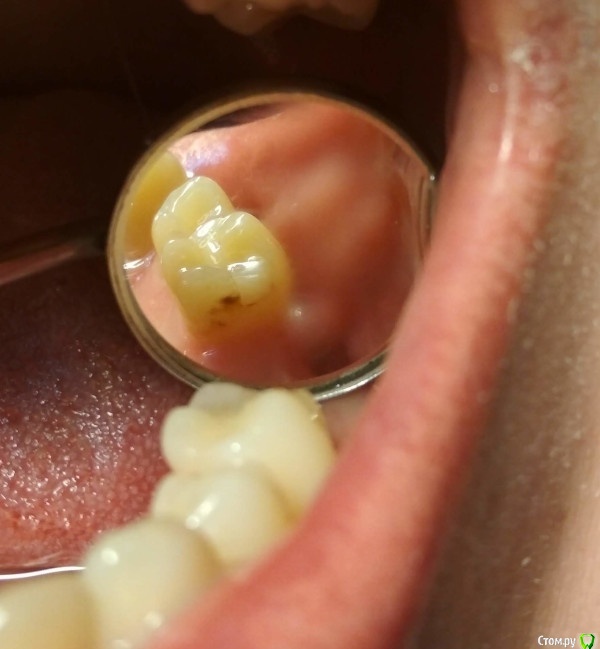

DenisB Опубликовано 13 октября, 2020 Поделиться Опубликовано 13 октября, 2020 Заметил на 35 зубе точку диаметром примерно 1 мм (см фото), стоматолог говорит, что это кариес в стадии пятна. На мой вопрос "как убрать" говорит, что такое они не лечат, сказала, что если ставить пломбу, то нужно её нужно будет переустанавливать каждые 3 года. Посоветовала использовать реминирализующий гель или реминирализующую пасту, как я понял это что-то типа rocs medical minerals.Вопрос: действительно ли можно убрать эту точку гелями/пастами? И если ставить пломбу, действительно ли её придётся переустанавливать каждые 3 года? Почему? Ссылка на комментарий

red_butler Опубликовано 13 октября, 2020 Поделиться Опубликовано 13 октября, 2020 По фото и панорамному снимку не понятна стадия кариеса, я бы скорее вёл его как кариес дентина, то есть пломбировал Ссылка на комментарий